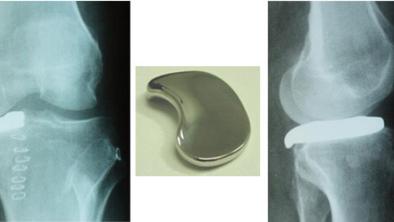

Apollo Hospitals organizes International OrthoGlide Workshop in Chennai

Indians are more prone to single compartment knee pain and that instead of total knee replacement, OrthoGlide implant and the new technique interpositional arthroplasty can be used as it doesn’t affect the ligaments of other compartments of the knee, says Dr Madan Mohan Reddy, senior consultant orthopaedic surgeon at Apollo Hospitals. On Saturday, Dr Klaus Lehrberger, renowned orthopaedic surgeon from Germany, provided a live demo of OrthoGlide and two patients underwent this procedure on the same day. The surgery, which is interpositional arthoplasty, is a minimally invasive knee surgery that involves an orthoglide implant, for early osteoarthritis where the arthritis is restricted to a single compartment of the knee. “It is between conservative treatment and total knee replacement,” said Dr Madan Mohan Reddy, senior consultant orthopaedic surgeon, during the workshop in which two patients aged 46 and 51 were operated on and the procedure was screened live. The doctors explained that the knee is divided into three compartments and Indians are prone to suffer osteoarthritis in the medial compartment of the knee. Earlier, doctors recommended either conservative treatment of suggesting weight reduction or lifestyle changes or the other extreme of undergoing a complete knee replacement, which was not just expensive – Rs 2 lakh – but also involves extensive post-operative therapy including physiotherapy. “This surgery is not just cost effective but also leads to faster recovery. A patient can get operated on in the morning and get discharged in the evening. The surgery doesn’t affect the ligaments in the other compartments of the knee,” explained Dr Madan Mohan. Dr Klaus Lehrberger said that the incision will be four to five centimeters and the implant is improvised in such a way that it requires no screw or bone cementing. “So far there has been no problem in stability of the implant post surgery,” he said. Apart from being cost effective, surgery costs Rs 1.3 lakhs with the implant alone at Rs 60,000, and fast recovery. Doctors said it can be used for younger patients, who can get back to their usual routine without any restrictions unlike complete knee replacement where the patient cannot sit on the floor or sit cross legged and so on. Dr Madan Mohan added that the surgery can be done on patients aged between 45 and 55 or even lesser. “Osteoarthritis is an aging process and happens both to men and women with the incidence of one in six persons above 55 years. The only way to prevent this is to maintain proper body weight, strengthen the knees and avoiding too much of sitting on the floor and Indian closets,” the doctor added. Dr Lehrberger said the technique was not a substitute for total knee replacement. “Compared to total knee replacement, this interpositional arthroplasty technique is much more invasive and after the procedure we have never seen any dislocation. No bone cut and no screws are necessary,” he said. In case of total knee replacement surgery, one requires physiotherapy for many days post-operation, but, in this case, patients can do some exercises taught by the doctors, he informed.